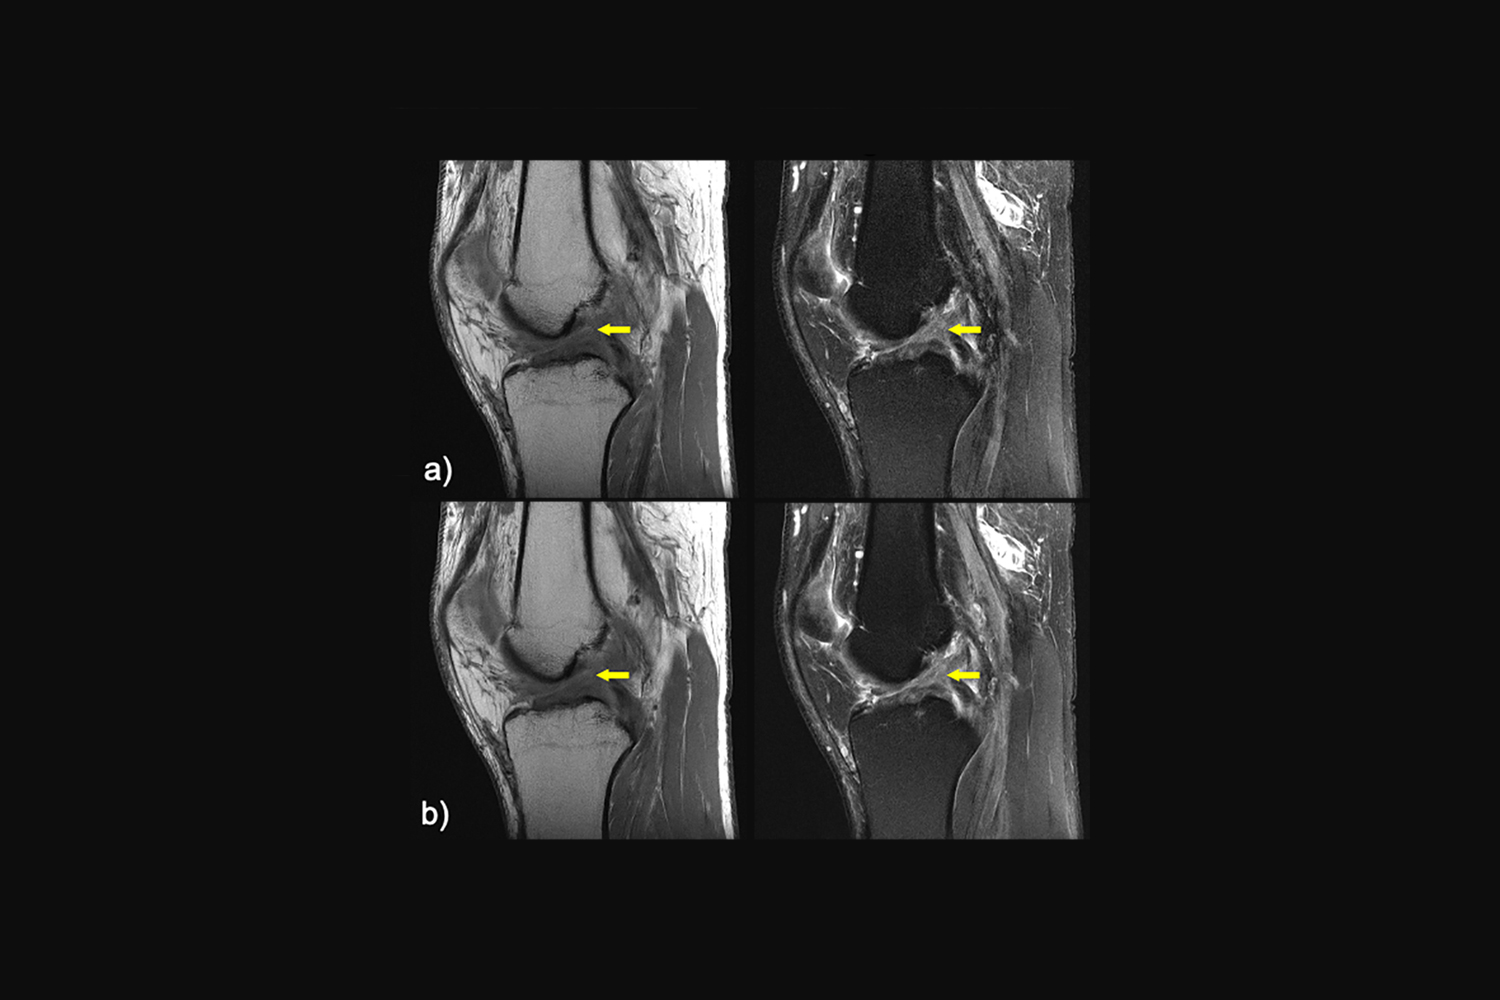

https://nyulangone.org/news/sites/default/files/2023-01/press-release-artificial-intelligence-reconstructs-data-mri-scans.jpg